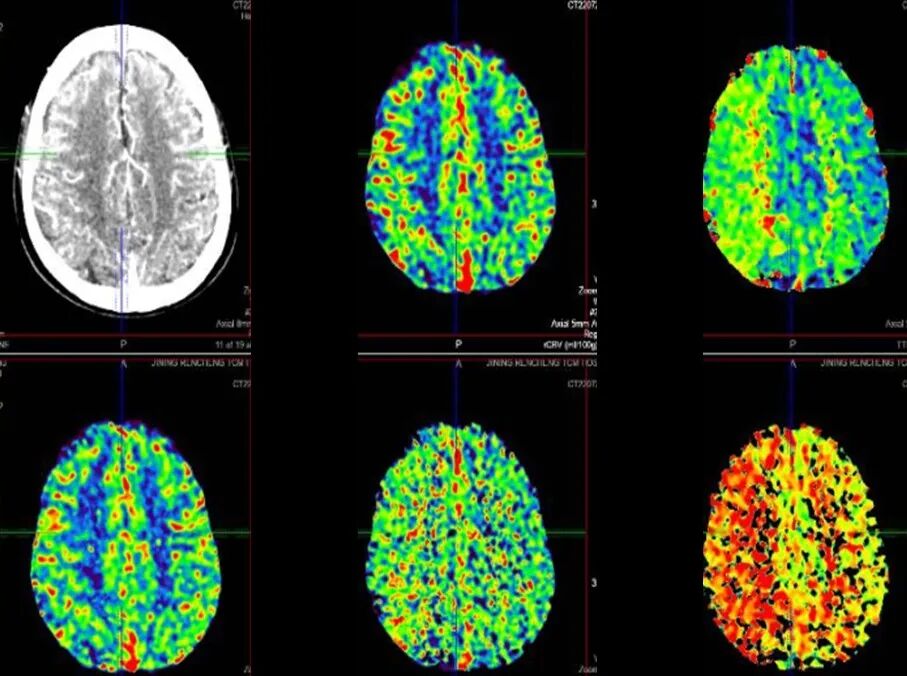

导丝怎么扩【载药时代 球扩天下】NOVA DES®颅内药物洗脱支架在颈内动脉颅内段重度狭窄的应用二例!_https://www.jmylbn.com_新闻资讯_第27张

DSA

重要影像结论:左侧颈内动脉C4段重度狭窄。